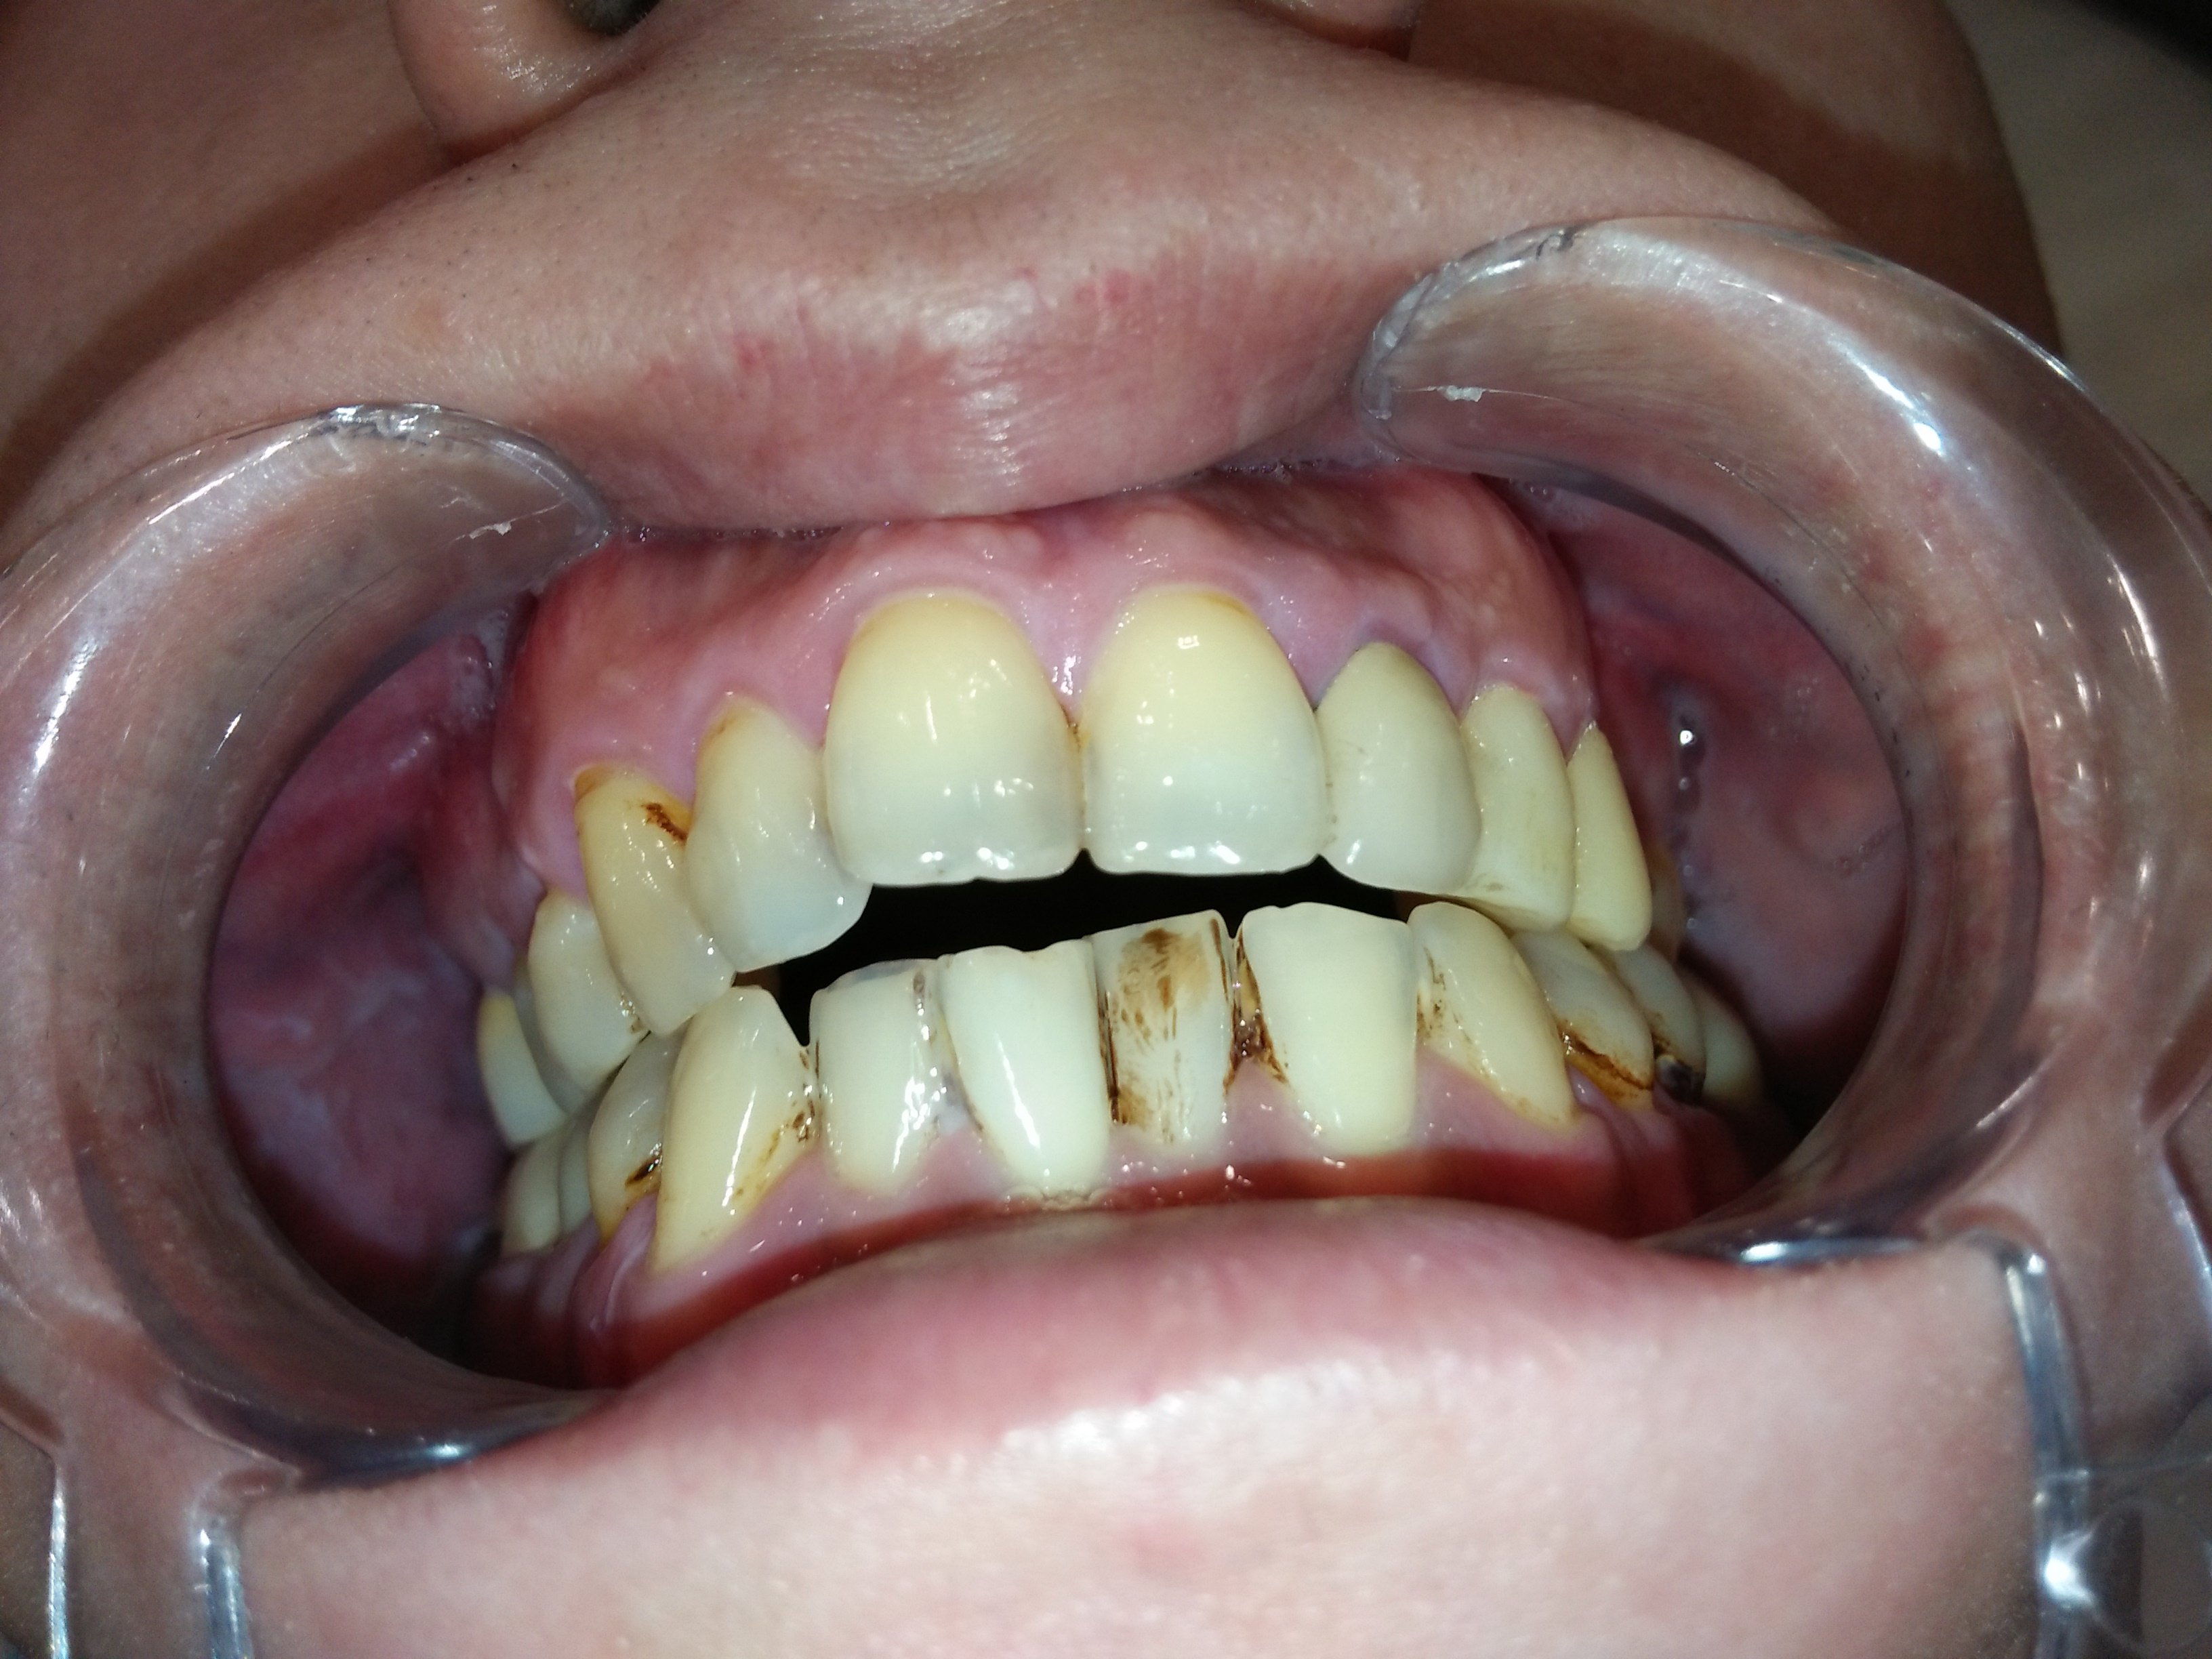

改變排列及牙齒上下相對位置,才能讓咬合和受力分配較佳並穩定,不會產生牙縫遭受直接衝擊的問題。

臨時的咀嚼一陣子並將咬合調順後,換成固定牙,更容易適應。